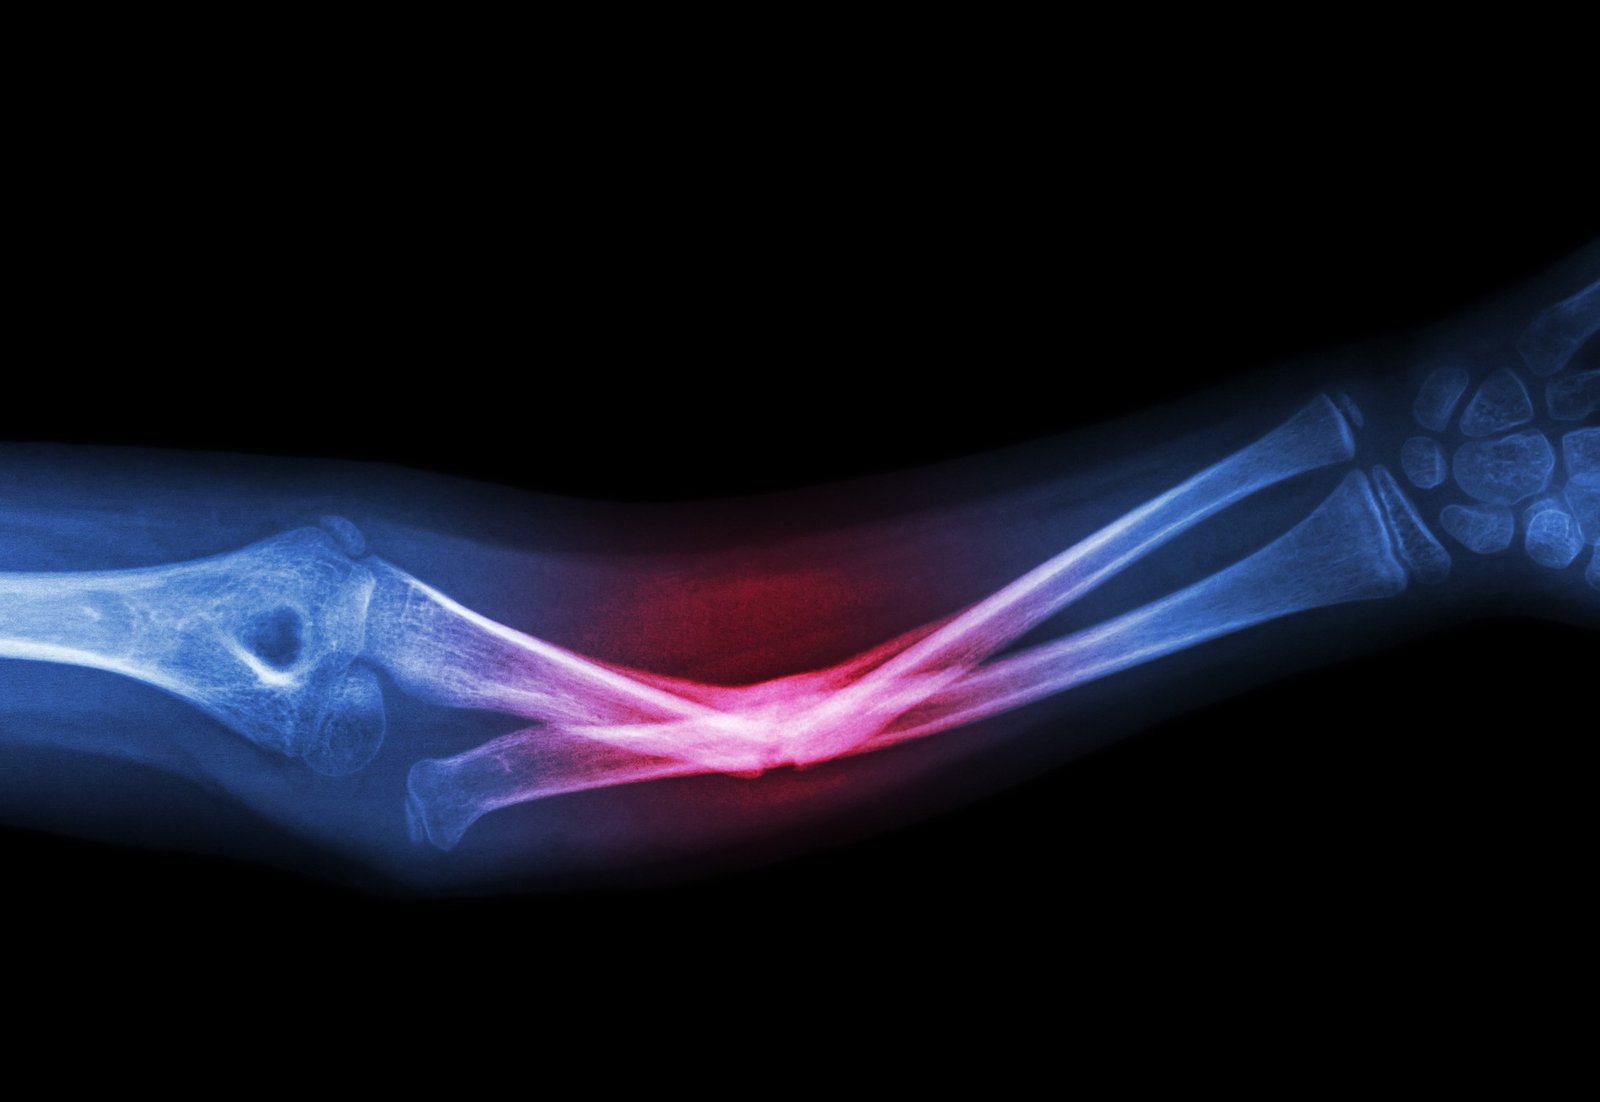

يتعرض الكثير من الأشخاص للإصابة بكسور العظام. ويُعد تأخر التئام كسور العظام (Delayed Union) وكذلك عدم التئام العظام (Nonunion ) وأيضًا التئامها بشكل خاطئ (Malunion fractures) من المضاعفات التي قد يتعرض لها الشخص المصاب بالكسور. وأسباب عدم التئام العظام متعددة، وهذه الأسباب المؤدية إلى صعوبة التئام كسور العظام يمكن تلافيها في كثير من الأحيان كما سنرى في ها المقال

عند تعرض العظام للكسر، يحدث نزف وتجمع دموي فى موضع الكسر ثم يبدأ الجسم مباشرة بعد بالعمل على إصلاح العظام المصابة. حيث تتكون جلطات دموية في مكان الكسر فتقوم بسد الأوعية الدموية التى تنزف.

المرحلة التالية هي تكوين الجسم لنسيج لين (callus) أساسه الكولاجين حول منطقة الكسر، بعد ذلك يتكون النسيج العظمي الصلب لتشكيل عظام جديدة. ثم تبدأ المرحلة النهائية وهي إعادة تشكيل العظام في منطقة الكسر حتى يتم الالتئام تمامًا وتعود العظام إلى شكلها الأصلي.